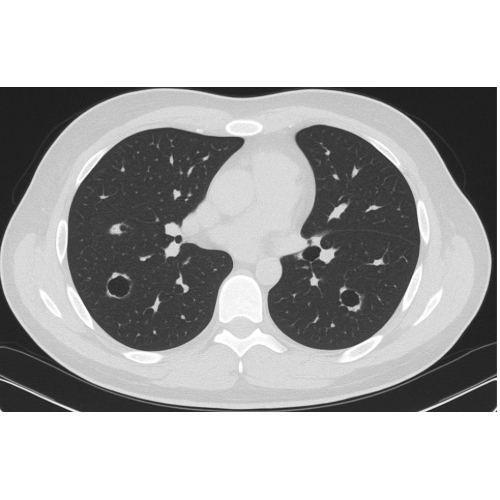

CT Chest with IV Contrast demonstrated air fluid levels, concerning for pulmonary abscesses secondary to septic emboli to the lungs.

Case Photo #2